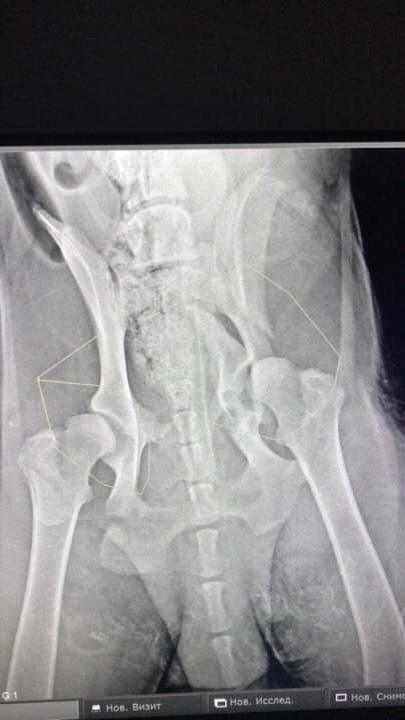

Двойной перелом таза без смещения. Чипа нет. Клеймо не рассмотреть -очень волосатое брюхо.

"надо показать снимки собаки специалистам,перелом со смещение,может надо оперировать и ставить пластину"

Фауста прооперировали